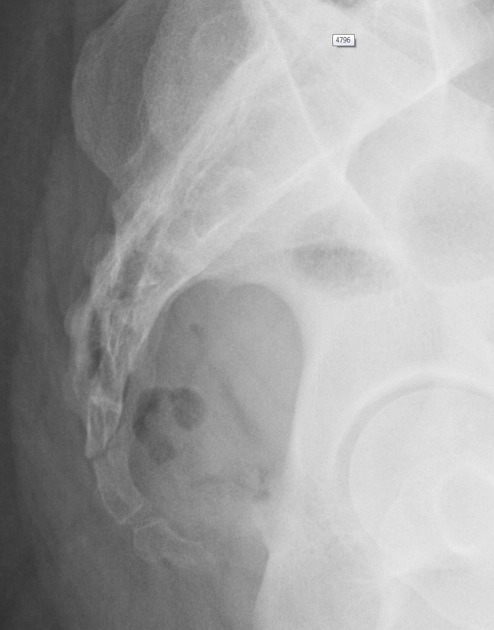

Gãy xương cụt (Coccygeal fracture)